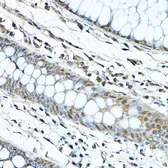

Images

Description

Applications